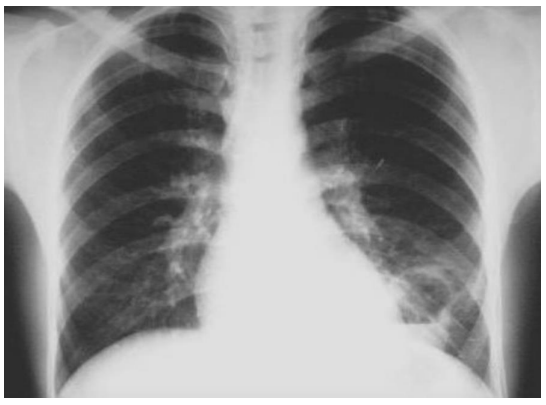

Carlos, 64 anos, dependente de álcool, em situação de rua. Deu entrada na Unidade de Pronto Atendimento com quadro de febre, dispneia e tosse produtiva há

4 dias. Refere ser HIV+ ainda sem terapia anti-retroviral. Radiografia segue abaixo:

Em relação à patologia em questão, qual seria o tratamento mais adequado?